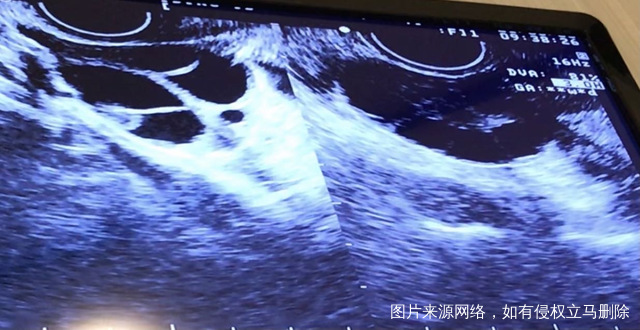

麻烦医生帮我看一下b超图,吃来曲唑后月经第十三天,我这一共大概有几个卵泡?左右卵巢各四个是吗?要不要紧?